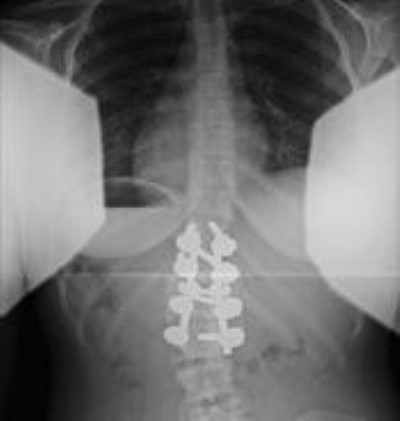

postoperative x-ray of congenital scoliosis

This X-ray was taken of the same patient after her surgery to remove the hemivertebra and fuse the curved vertebrae with a metal implant.

Courtesy of Scottish Rite for Children, Dallas

Hemivertebra removal. A single hemivertebra can be surgically removed. The partial correction of the curve that is achieved by doing this can then be maintained using metal implants. This procedure will only fuse two to three vertebrae together.